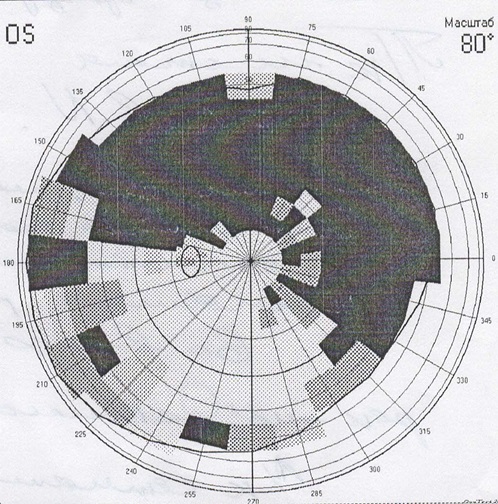

1. Perimetry. A frequent symptom of detachment is «veil» or «curtain» in front of the eye, it looks like this:

1.视野测定法。 眼球脱离的常见症状是眼前的“面纱”或“窗帘”,看起来像这样: